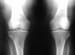

In major weight-bearing joints, a greater loss of joint space occurs at those areas subjected to the greatest pressures; this effect is in contrast to that of inflammatory arthritides, in which uniform joint-space narrowing is the rule. In the osteoarthritic knee, for example, one commonly observes the greatest loss of joint space in the medial femorotibial compartment (see the image below), although the lateral femorotibial compartment and patellofemoral compartment may also be affected. Collapse of the medial or lateral compartments may result in varus or valgus deformities, respectively. Hence, weight-bearing radiographs are preferred for evaluation of the osteoarthritic knee to depict such deformities, as well as to provide an accurate assessment of joint-space narrowing.

Standing anteroposterior (AP) radiograph of the knees reveals bilateral medial femorotibial compartment narrowing and sharpening of the tibial spines; this finding is typical of osteoarthritis.